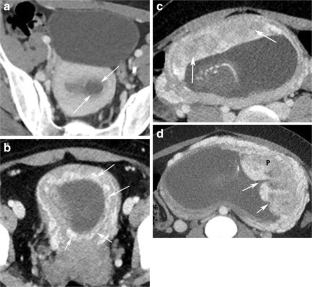

Fig. 1